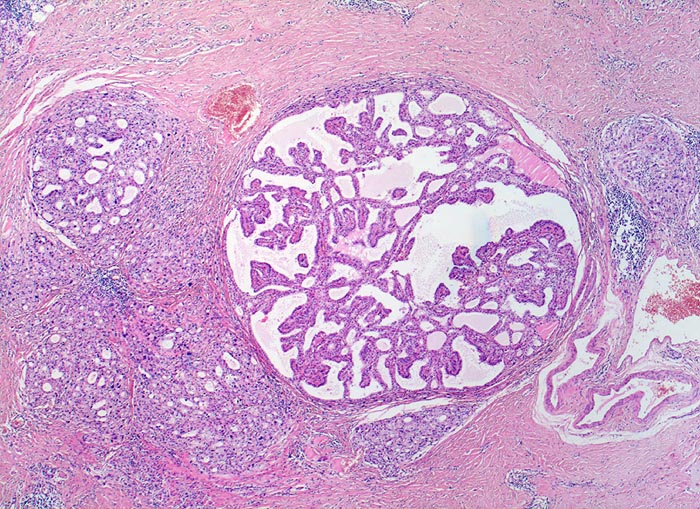

Hashimoto Thyreoiditis mit Resten eines Morbus Basedow

Ausgeprägte Vernarbung des Parenchyms mit herdförmigem chronischem Entzündungsinfiltrat. Kleintubuläre und solide Parenchymanteile, sowie kleine kolloidfreie Follikel. Ausserdem ein Regeneratknoten mit pseudopapillären Formationen.

Vor 2 Jahren beidseitige Strumektomie. Exophthalmus und Myxödeme der Unterschenkel.

Gelegentlich kann eine Basedow-Hyperthyreose in eine Struma lymphomatosa Hashimoto mit Hypothyreose übergehen (sog. Hashitoxikose), was die z.T. fließenden Übergänge zwischen den einzelnen Formen der Immunthyreopathien verdeutlicht.